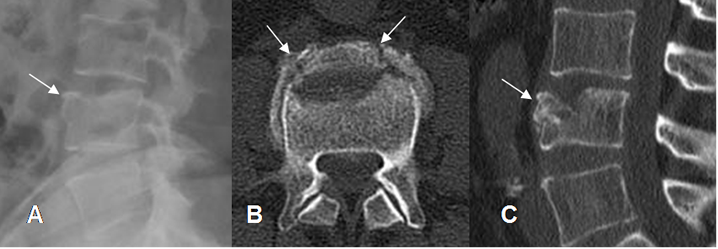

Fig 204. Fractura del paleador.

A: Rx lateral. No se aprecian alteraciones, pero solo son evaluables 5 cuerpos vertebrales.

B: TAC axial y C: TAC reconstrucción sagital. Fracturas no desplazadas en las apófisis espinosas de C6 y C7.

Fig 205. Fractura del paleador.

A: Rx lateral. Fractura desplazada en la apófisis espinosa de C6.

B: RM axial en T2 y C: RM sagital en STIR. Cambios inflamatorios en los tejidos blandos e hiperintensidad, por lesión de los ligamentos interespinosos.